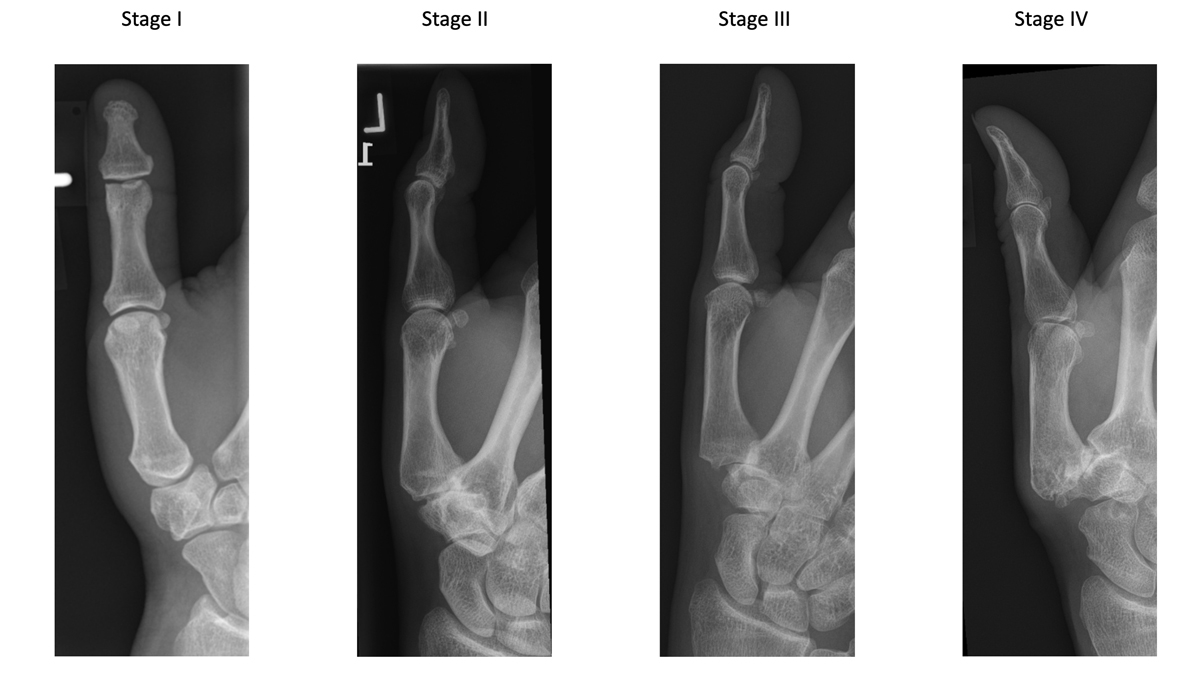

In 1987, Eaton and Littler proposed a radiological classification of trapeziometacarpal osteoarthritis, which is still the most widely used for staging. This classification system consists of four different stages (fig. 1) [16, 17]. Even though other imaging techniques and classification systems exist, X-rays of the thumb in two planes remain the gold standard and should be ordered early in suspected TMO [16, 17]. It is, however, important to evaluate the neighbouring joints such as the scaphotrapezial and scaphotrapezoidal (STT) joints for treatment.

Figure 1 Eaton/Littler classification of trapeziometacarpal osteoarthritis.

Stage I: slight widening of the joint space and normal contours.

Stage II: slight narrowing of the TMC and sclerosis, osteophytes <2mm, up to 1/3 subluxation of the joint

Stage III: marked joint space narrowing, osteophytes >2mm, >1/3 subluxation

Stage IV: Pantrapezial arthritis, major subluxation, cystic and sclerotic subchondral bone changes, significant erosion of the scaphotrapezial joint.